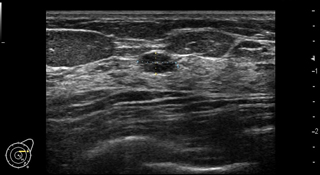

乳腺が発達している若い世代でも、しこりが見つけやすく、小さなしこりも発見できるのが特徴です(検査画像サンプルその1・2)。一方、乳がんの石灰化を画像に映し出すことは難しく、がんが見落とされる心配があります。

当院の超音波診断装置では、乳腺組織の硬さまでわかるようになっており、触診の代わりに画像で確かめることができるようになってきています。放射線被ばくがないため、妊娠中の女性でも検査を受けることが可能です。痛みを伴わず、身体的苦痛がないのもメリットです。